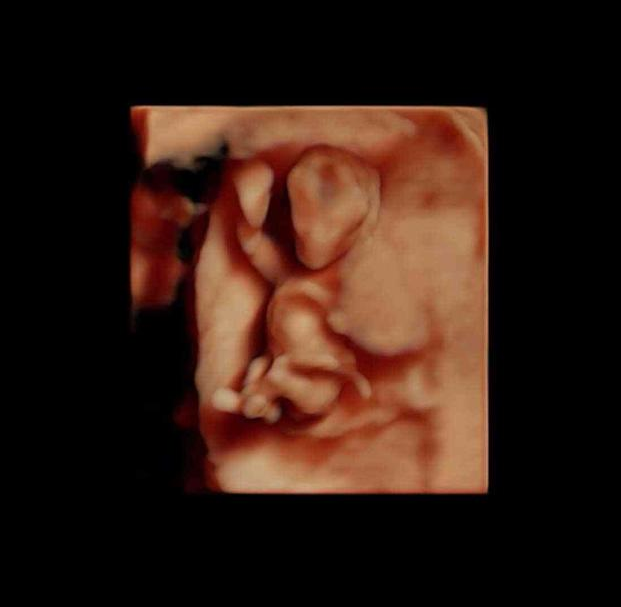

在上图可见是个双胎妊娠,胎儿具有一个很大的头,和身材很不对称,是不是跟出生后的胎宝宝有点像了?其实此时的头部比例更悬殊,宝宝的额面部器官发育很明显,心脏也开始了跳动,出现了胎心,此时做B超,可见震了厘胎心胎芽。